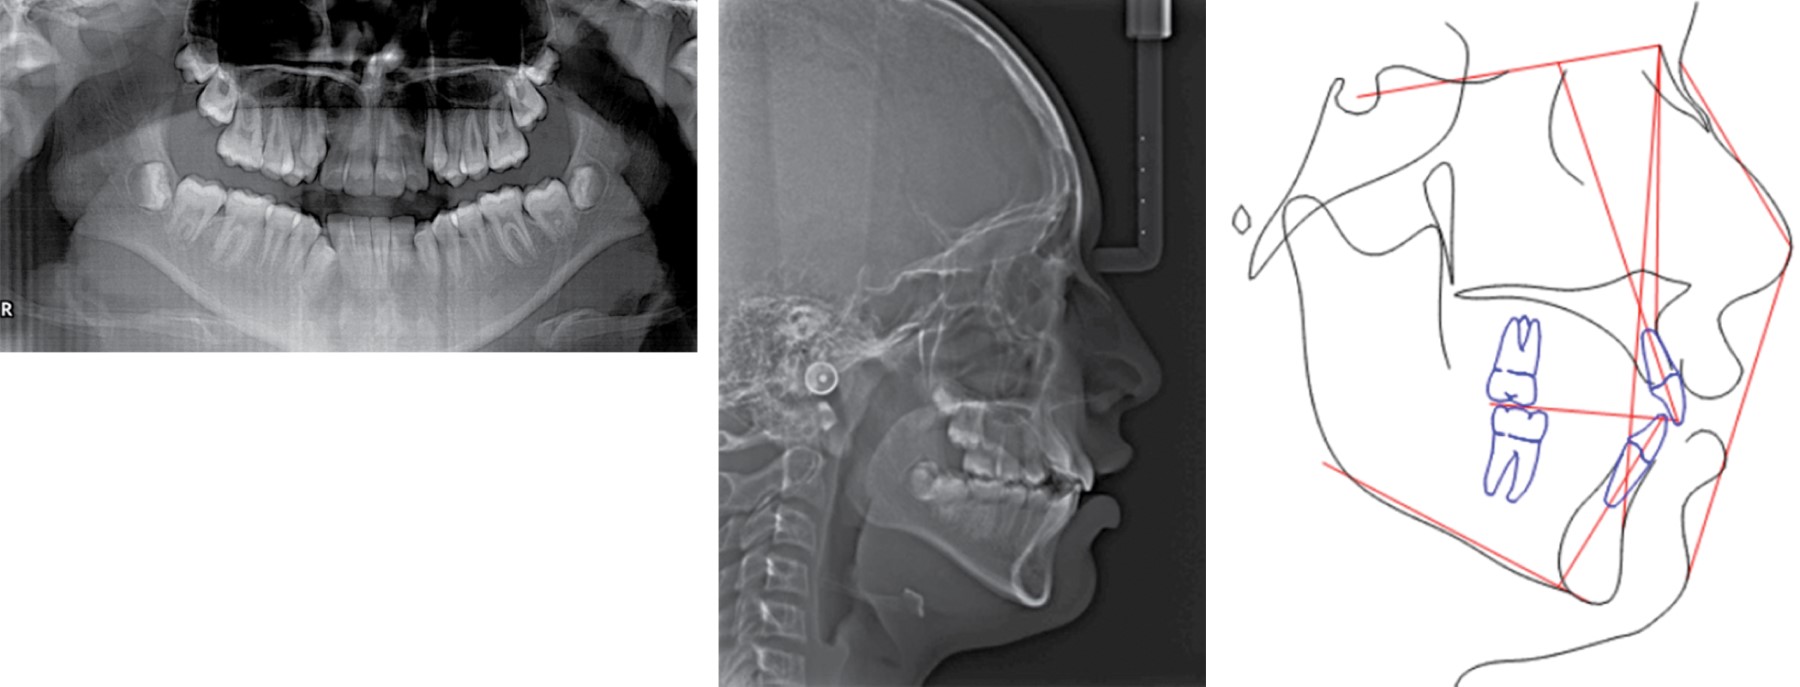

Al examen clínico la paciente presentó desarrollo normal, con un biotipo dolicofacial, perfil convexo, tercio inferior aumentado, línea media facial coincidente con línea media dental (Figura 1). En el análisis intraoral se observó clase I molar, clase canina no establecida por caninos superiores ectópicos, mordida cruzada posterior unilateral derecha, incisivos inferiores proinclinados y protruidos, forma de arco superior triangular e inferior ovoide, línea media inferior desviada 2 mm a la izquierda, sobremordida horizontal 3 mm y vertical 3.5 mm (Figura 1), discrepancia de longitud de arco maxilar de -9.8 mm y mandibular de -10.9 mm, curva de Spee de 2 mm (Figura 2). Radiográficamente se observó dentición permanente, cornetes semipermeables, asimetría de cóndilos, presencia de germen de terceros molares y premolares inferiores sin cierre apical. En la radiografía lateral de cráneo se observaron vías aéreas permeables e incompetencia labial (Figura 3). Se realizó el trazado cefalométrico de Steiner con el software Dolphin 9.0 y se resolvió en una clase II esqueletal con posterorrotación mandibular (Tabla 1). El análisis funcional no presentó alteraciones en la articulación temporomandibular ni hábitos.

Figura 3